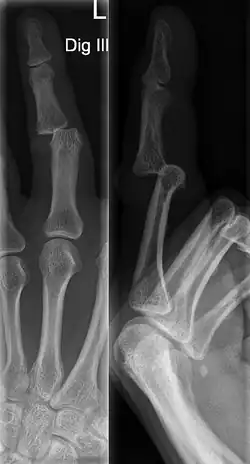

A jammed finger can generally be diagnosed by a physical examination. Bone or joint deformity may indicate potential dislocations or fractures.[6] The basic structure of the finger includes three bones with joints in between each.[9] The joint closest to the tip is the distal interphalangeal (DIP) joint. The next joint, moving closer to the hand, is the proximal interphalangeal (PIP) joint. The thumb differs by only having two bones and one interphalangeal joint.[10]

The injured finger may be examined to determine where the pain is worst.[3] If the finger is sprained or dislocated, pain will be worse at the joint rather than the bone.[3] Due to the risk of dislocations or fractures, X-rays should be conducted prior to testing joint stability. This allows for prior detection of a dislocation or fracture.[3] It is recommended that a variety of views (lateral, oblique, and anteroposterior) are observed.[3] In extremely painful cases, a digital nerve block may be done to better assess the finger. This is where anesthetic is injected to either side of the base of the affected finger to reduce pain.[3]

Injuries that force the finger towards the back of the hand may cause damage to the volar plate.[12] This is a ligament on the palm side of the hand that prevents hyperextension.[13] Volar plate damage may be assessed by pressing the finger bones from the back towards the palm. If either individual bone of the affected joint moves freely towards the palm, it is indicative of a tear.[2] Tears of the volar plate may lead to an avulsion fracture – when a piece of bone is pulled off with the ligament.[13] This is due to the thickness and strength of the ligament.[14] To rule out an avulsion fracture, x-rays are frequently utilized in evaluation of suspected volar plate tears.[12] Volar plate avulsions are most evident on lateral views.[2]

DIP dislocations are much less common than PIP dislocations.[3] This is thought to be due to the increased stability of the DIP joint,[15] though not for certain.[2] Dislocations can be categorized based on the direction that the fingertip moves in relation to the knuckle.[6] If in the direction of the palm, it is a volar dislocation. If in the direction of the back of the hand, it is a dorsal dislocation.[6] If in the direction to either side, it is a lateral dislocation.[2] Of the three, dorsal dislocations are most common.[6] Dorsal dislocations of the PIP commonly lead to volar plate damage.[2]

Dislocations are often visually obvious due to joint deformity.[2] Therefore, x-rays may or may not be utilized in the diagnosis of a suspected dislocation. Though, they can provide feedback on post-reduction status if attempted prior to formal medical evaluation.[2] Dislocations may also be complicated by a tandem fracture.[5] These cases may necessitate a visit to a hand surgeon for surgery.[2]

Fractures

Fractures are instances where the bone's structural integrity has been compromised.[20] If a jammed finger produces a fracture, pain will be greatest at the bone as opposed to the joint.[2] There may also be visual deformation of the bone itself.[6] As with any skeletal injury, an x-ray can be conducted to verify the presence of a fracture.[1] The distal phalanx is especially vulnerable to avulsion fractures.[1] These avulsion fractures are common following a first time dislocation of the DIP.[1]